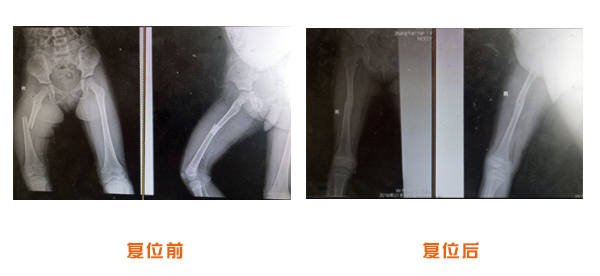

肥城市安駕莊梁氏骨科醫(yī)院是一所以梁氏手法正骨配合膏藥為特色的現(xiàn)代化??漆t(yī)院。

梁氏骨科術(shù)始創(chuàng)于清雍正年間,歷經(jīng)八代,至今已有三百年歷史。據(jù)1929年泰安縣志載“梁瑞圖先生,字增生,號(hào)蓮峰,安駕莊人,精岐黃并發(fā)明接骨,凡跌打車凡跌打車軋皮不破而碎骨者......【詳細(xì)】 |